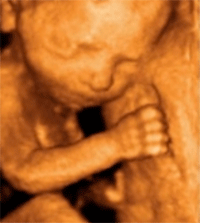

Если полвека назад при проведении ультразвукового исследования реально было увидеть лишь отдельные детали анатомии, то сегодня можно рассмотреть даже мигание век плода. Собственно, возможность исследовать значимые нюансы – заключается обязательная, по мнению большинства врачей, практика УЗИ-диагностики.

Основной задачей УЗИ этого периода становится пренатальная диагностика возможных врожденных уродств. Анализируются фетометрические показатели плода — от межтеменного размера головки, длины бедренной кости до окружности живота. УЗИ позволяет изучить также анатомические особенности сердца, легких, печени, селезенки, желудка, почек, кишечника, мочевого пузыря. Если обнаруживаются пороки, однозначно несовместимые с жизнью, то у женщины еще имеется печальная возможность прервать беременность.